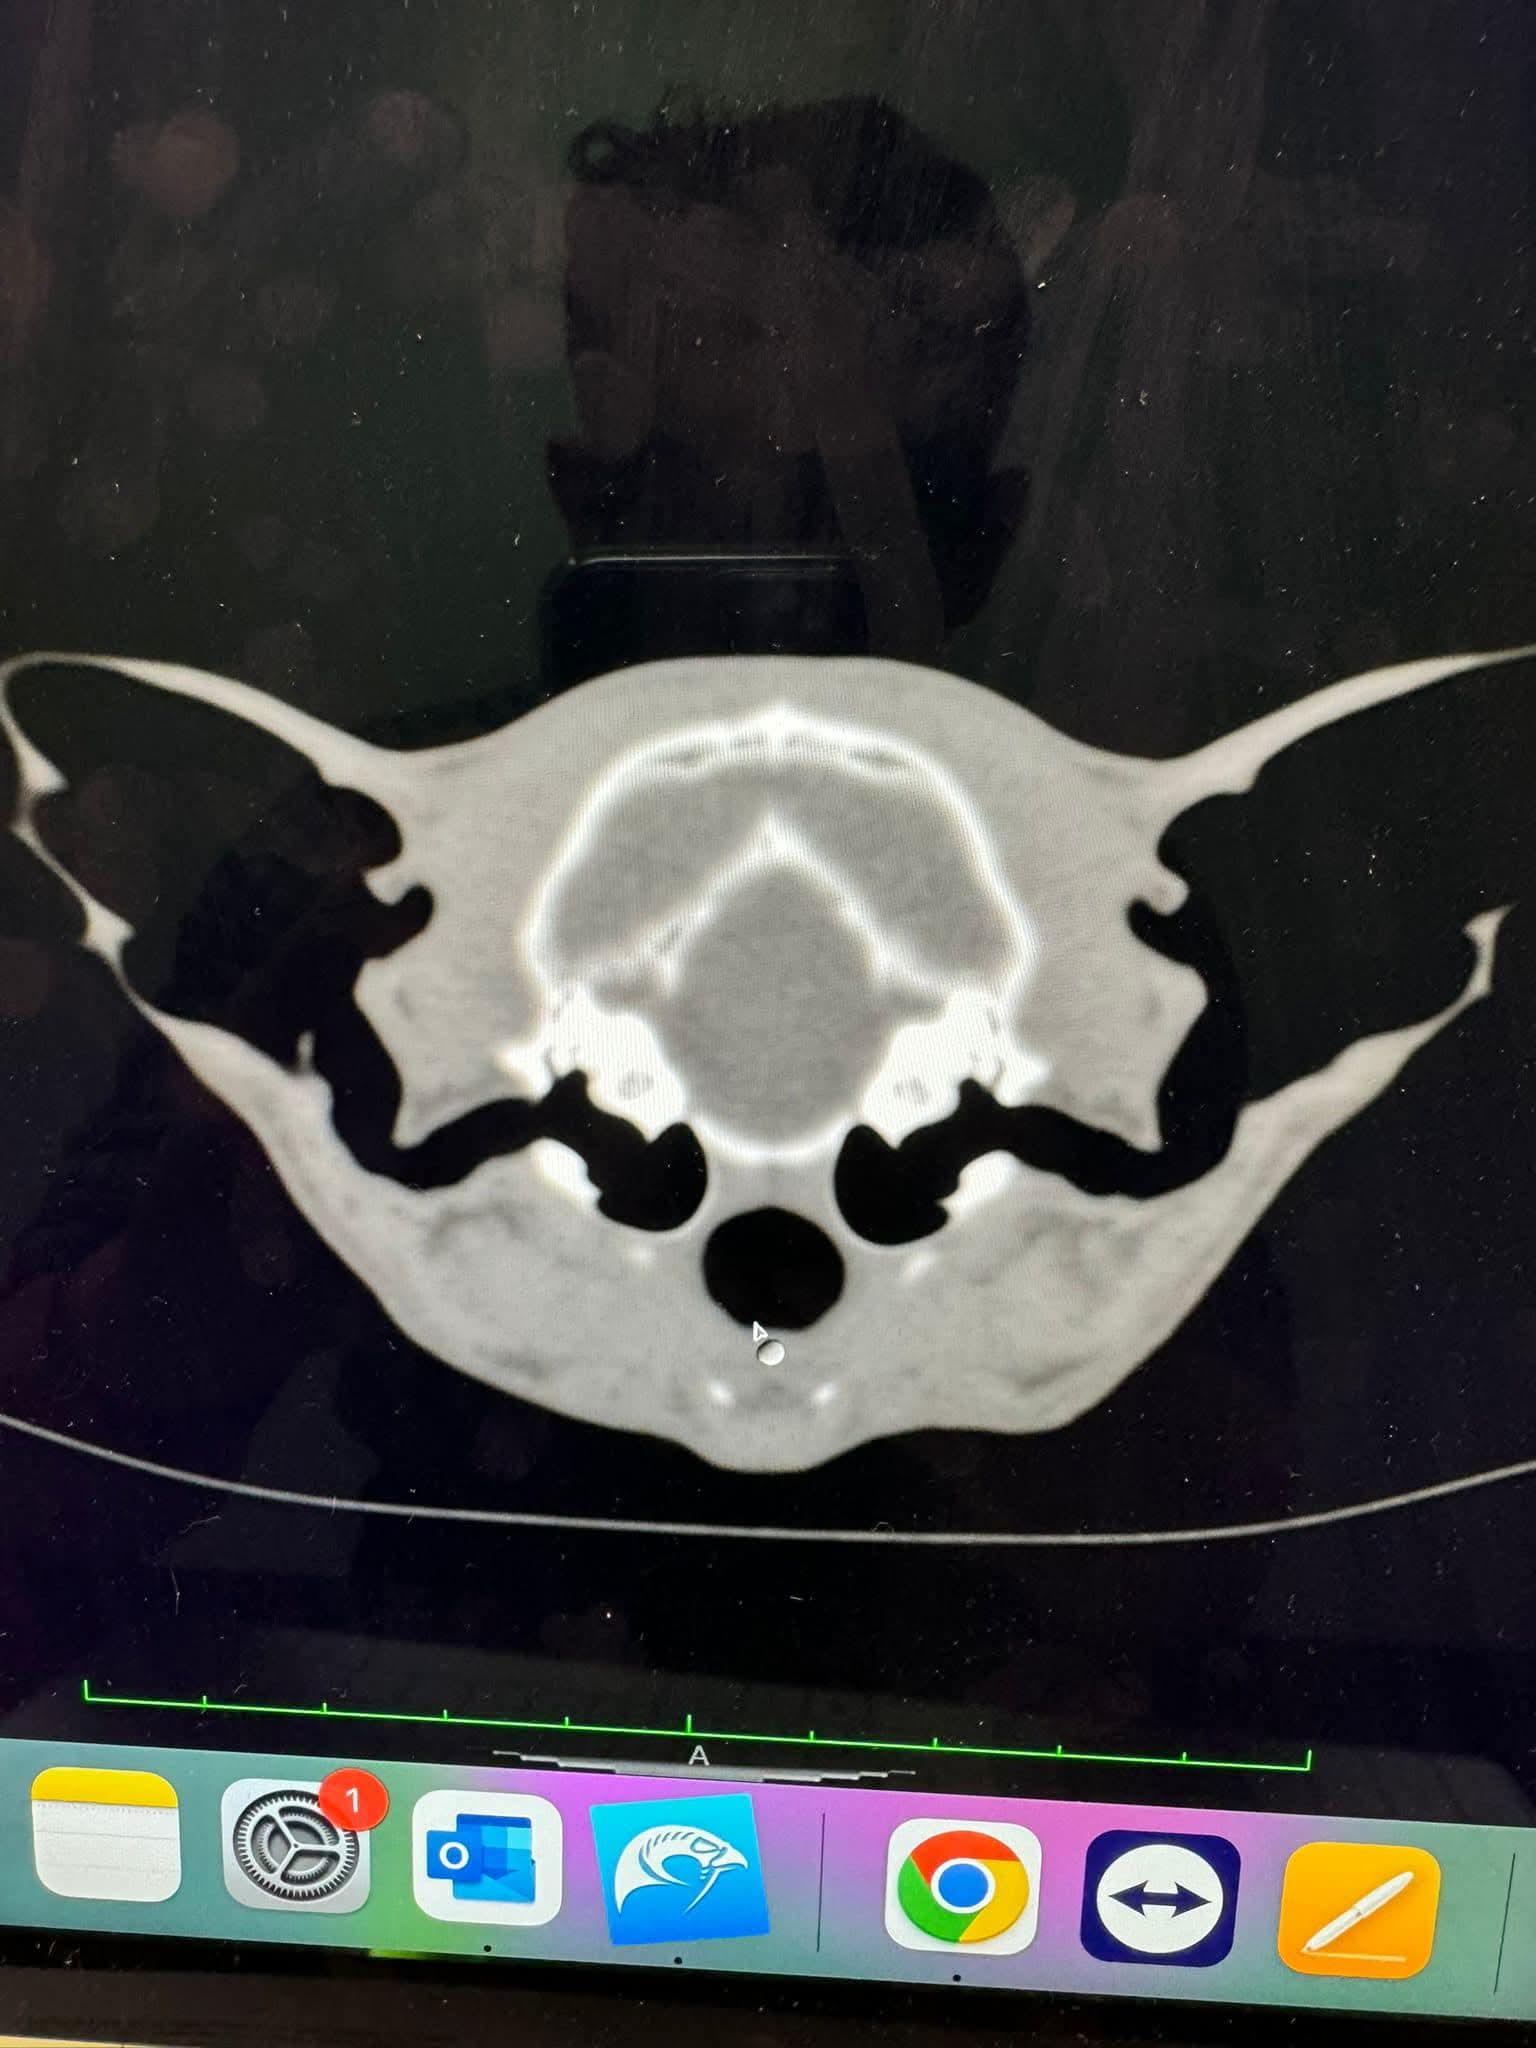

CT Scanner

Our CT scanner was installed at our Tunstall practice in 2017 and was the first permanent veterinary CT scanner in our area. It is available 24 hours a day to both our own patients and as a referral service to surrounding practices.

Computed Tomography (CT) involves the use of x-rays to take thousands of pictures of cross-sections of the body. These can then be built up into a 3D image and used to create a detailed reconstruction of the patient. This is a thorough and prompt way to reach a diagnosis and enable quicker treatment. The CT scanner is particularly useful for the diagnosis and planning of complex surgical procedures and medical conditions.

We are able to obtain full results from external specialists and also, we are lucky that one of our own vets - Charlie Green - is an Advanced Practitioner is Diagnostic Imaging and a General Practitioner in CT; meaning she can read our CT scans on site and enhance surgical planning and treatments.

Brian’s CT Scan

The first CT scan we carried out was done on Clive's dog, Brian's, nose. We found a sarcoma in his upper jaw, and successfully removed it. A CT was needed to ensure the surrounding area was in good health.